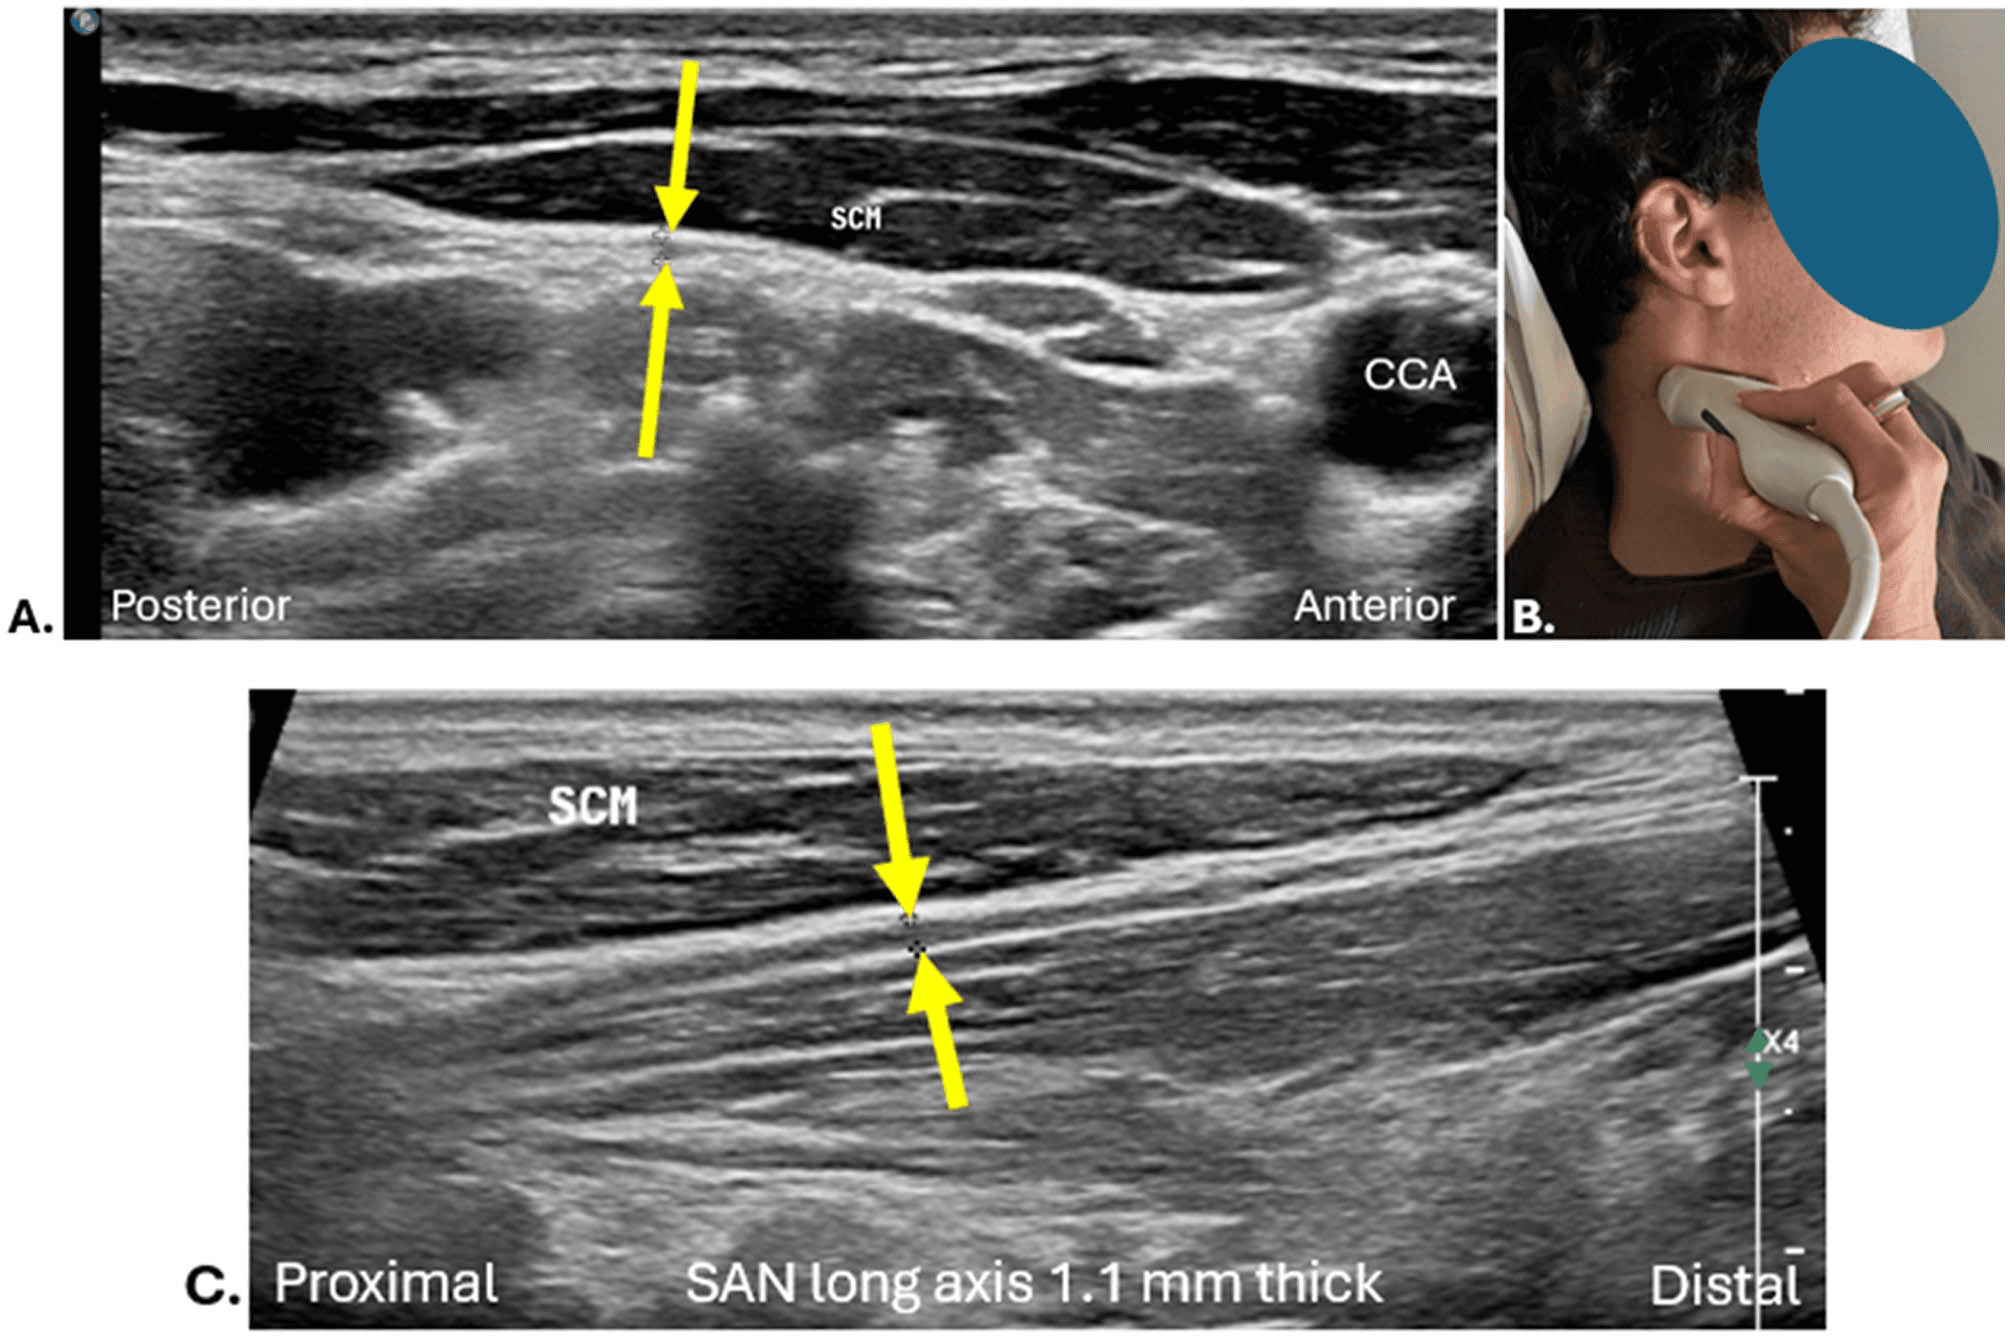

흉쇄유돌근 - 그림 4. 흉쇄유돌근(sternocleidomastoid, SCM) 심부를 주행하는 척수부 Figure 4. 그림 4. 흉쇄유돌근(sternocleidomastoid, SCM) 심부를 주행하는 척수부신경(SAN)입니다. (a) 단축 정적 영상입니다.

흉쇄유돌근 심부를 주행하는 척수부신경의 초음파 영상에서는 근육 섬유 사이로 지나가는 신경의 모습을 단축면에서 명확히 관찰할 수 있습니다.